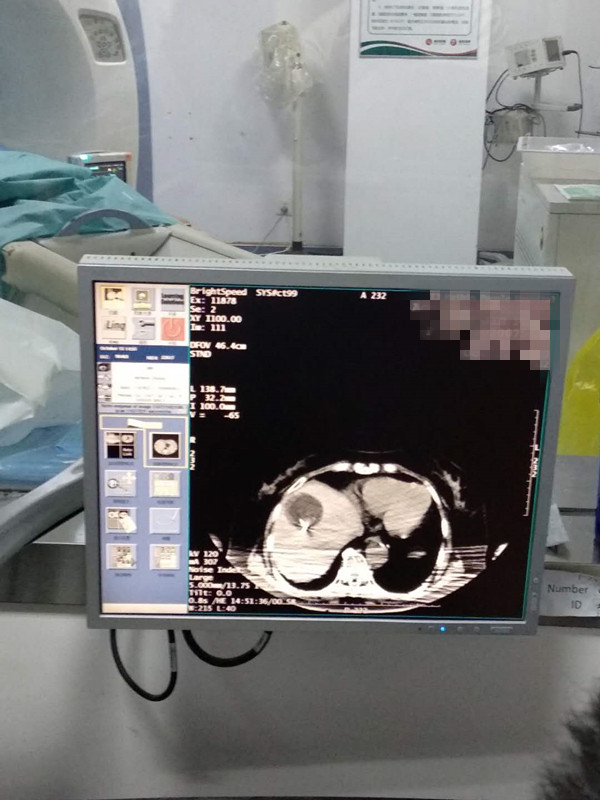

73岁患者肝部氩氦刀冷冻消融